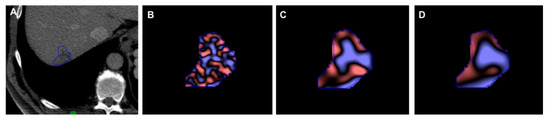

2.5. Texture Analysis

3.2. Differences in Texture Features

3.3. Diagnostic Criteria Based on Results of CT Texture Features